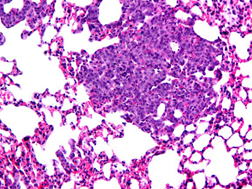

結(jié)節(jié)多、結(jié)節(jié)少

圖1 HE染色示意圖 100X

樣本中細(xì)胞核被蘇木精染成鮮明的藍(lán)色。細(xì)胞質(zhì)被伊紅染成深淺不同的粉紅色至深紅色。對比鮮明??梢郧逦^察到組織形態(tài),符合HE染色結(jié)果的要求。